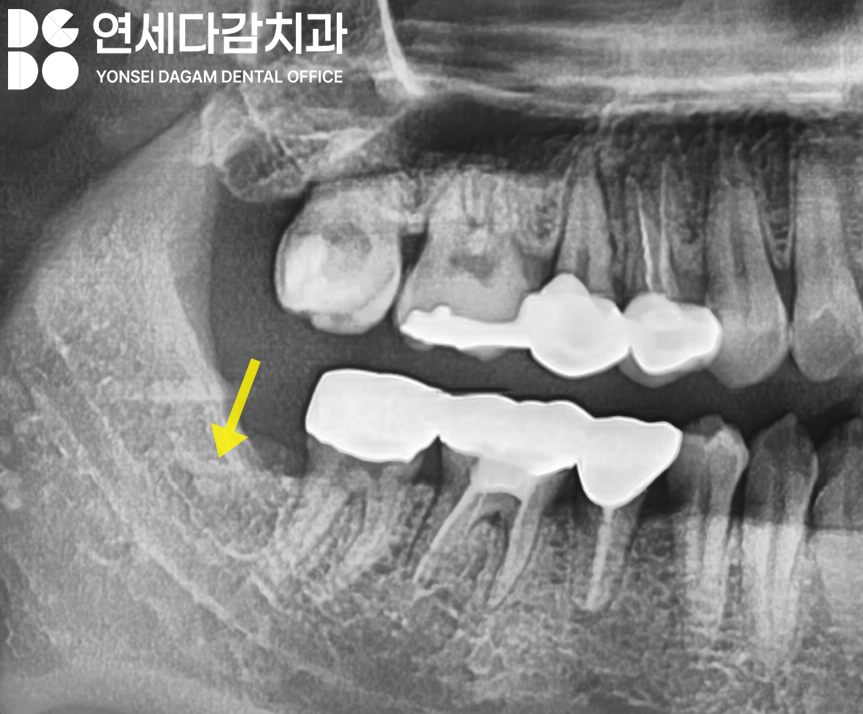

수평으로 매복된 경우,

CT 분석 결과 하치조신경과

근접해 있는 경우가 많습니다.

하치조신경은 아래턱의

감각을 담당하는 주요 구조물이므로,

손상되면 감각이상이 생길 수 있습니다.

따라서 오금동 치과 에서 보여드린

해당 케이스에서도

극도로 조심스러운

접근이 필요합니다.

마찬가지로 사전 분석을 통해

치료 전략을 세우고,

계획에 따라 분할 발치를

시행하여 치아 조각이

남지 않도록 깔끔하게 치료를 완료합니다.

이가 나온 부위는

점차 자연스럽게 치유되며,

12개월 이후 정기검진에는

뼈가 안정화되어

오금동 치과 에서 보여드린

X-ray 상에서 밀도가

높아진 것을 확인할 수 있습니다.